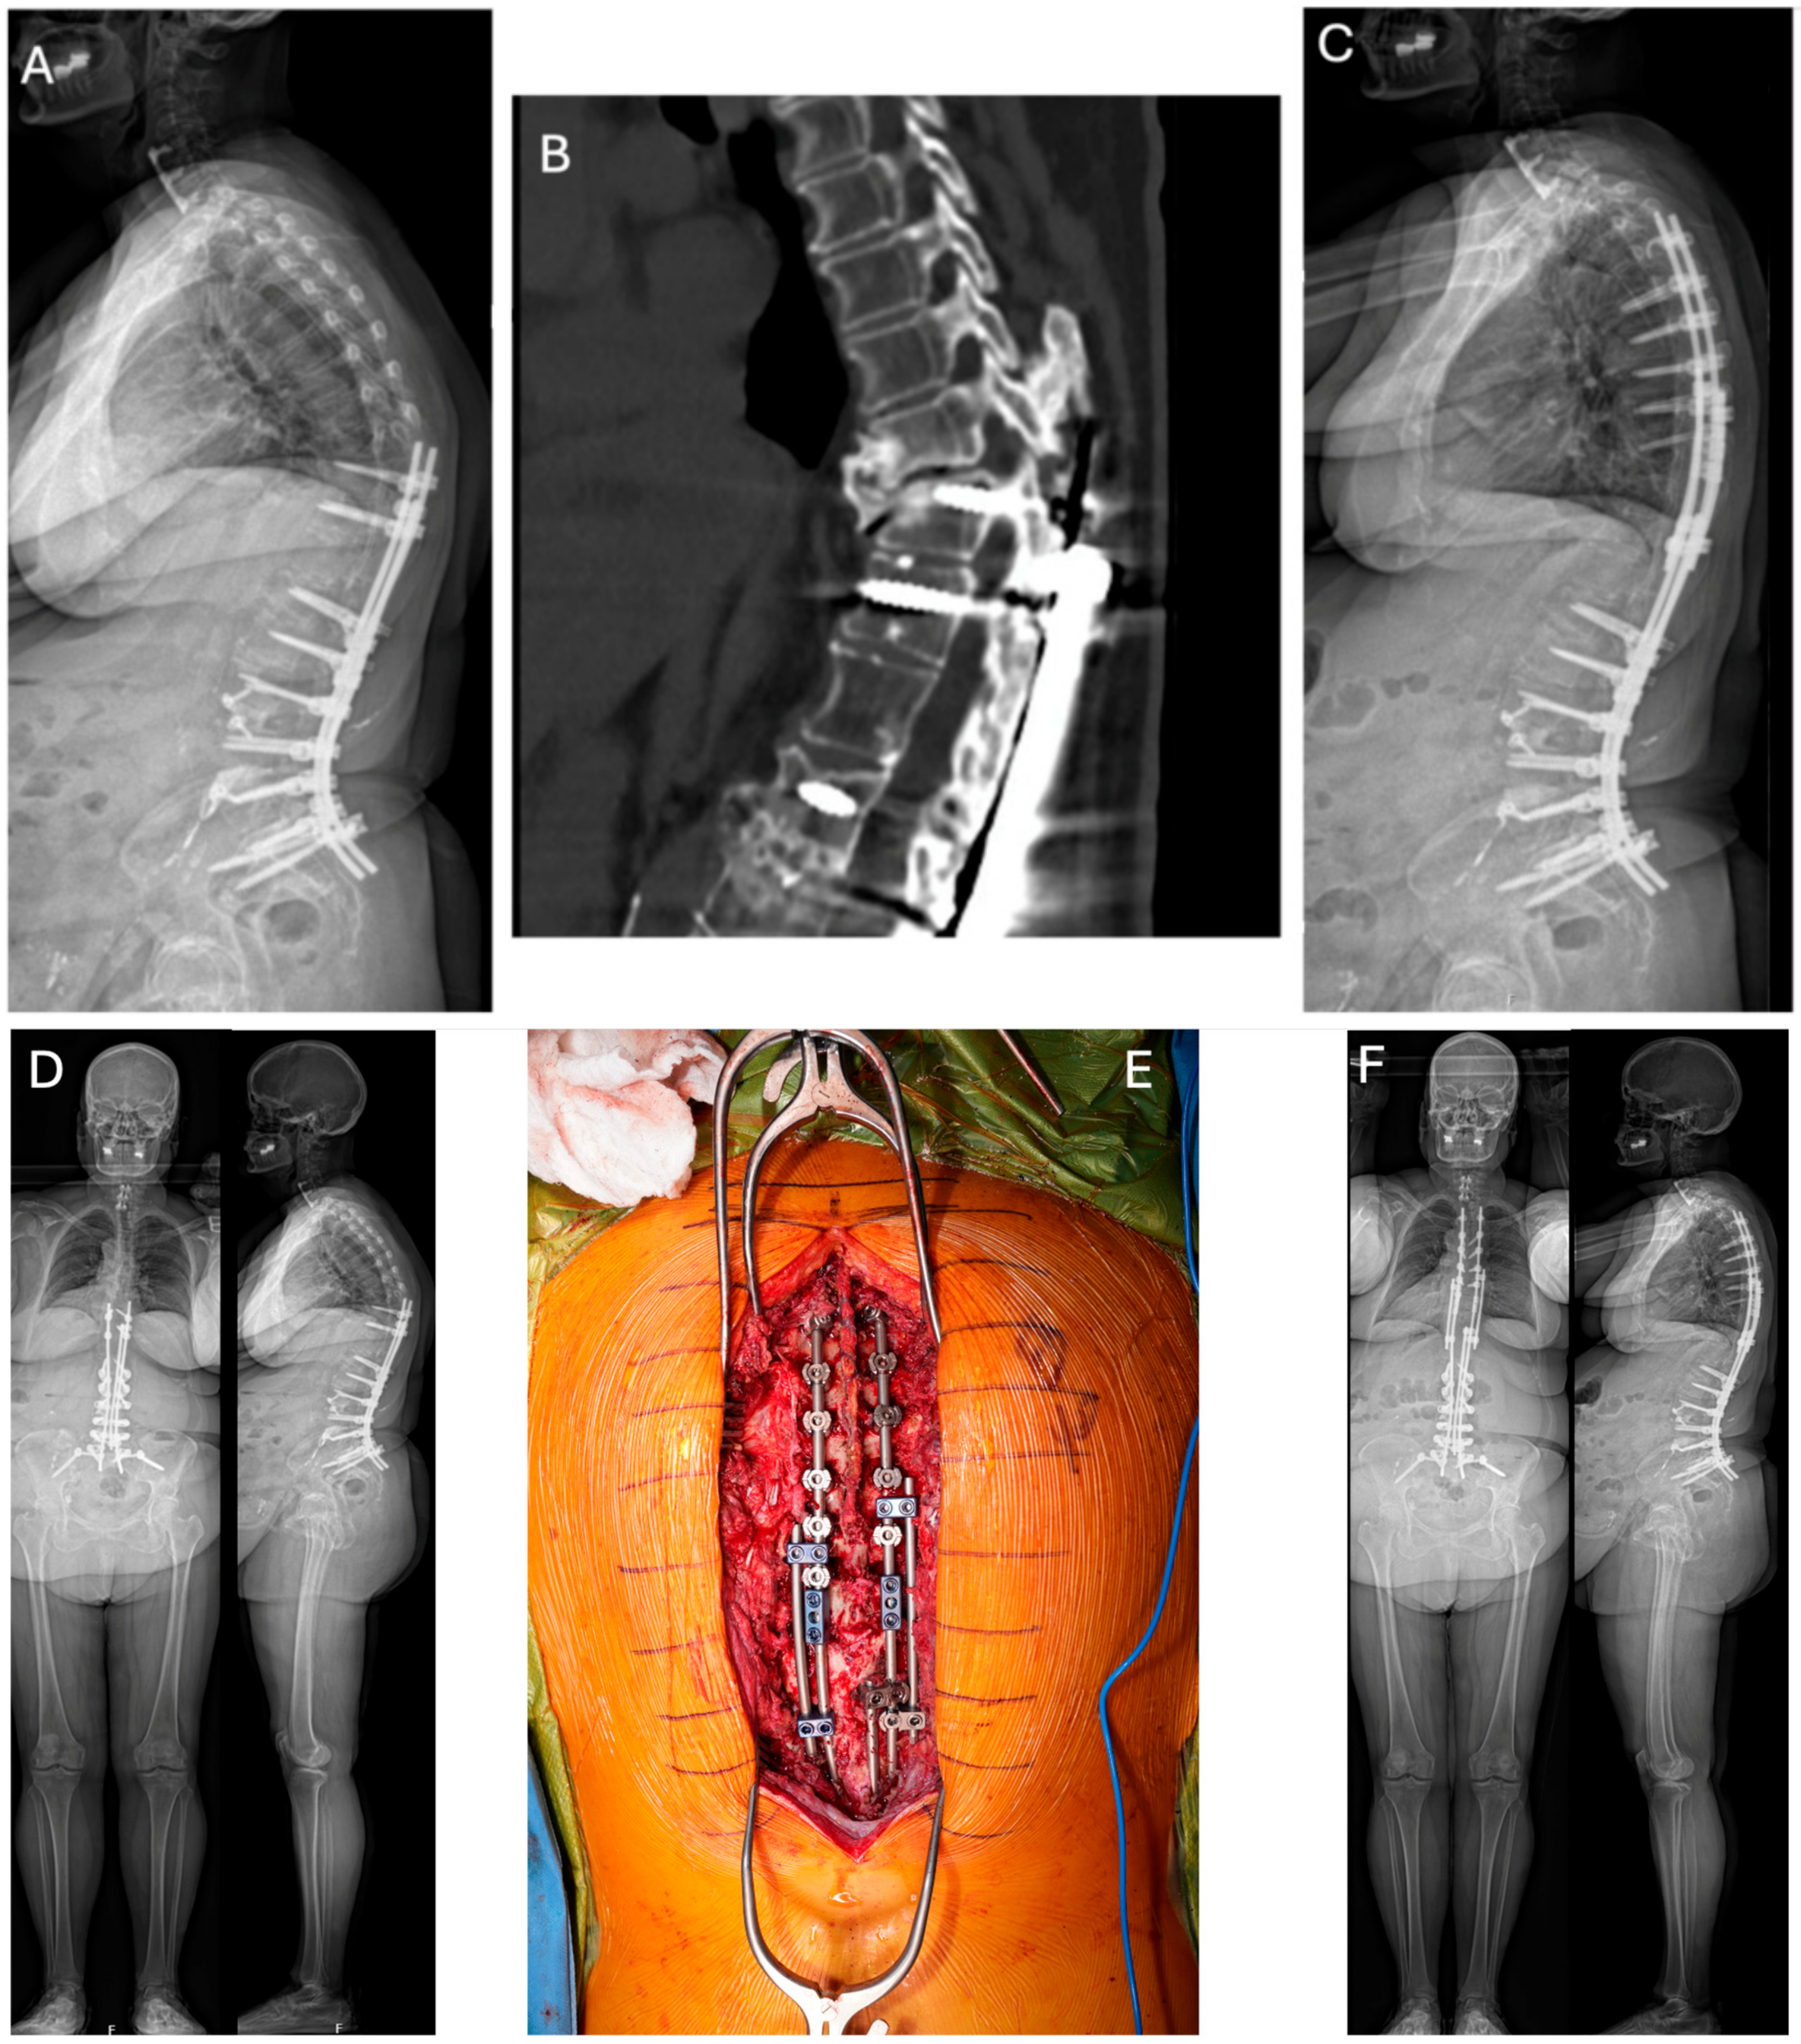

2. Part I: Rod Fracture

2.5. Treatment Strategies

2.6. Prevention Strategies

3. Part II: Proximal Junctional Kyphosis and Proximal Junctional Failure

3.5. Treatment Strategies

3.6. Prevention Strategies